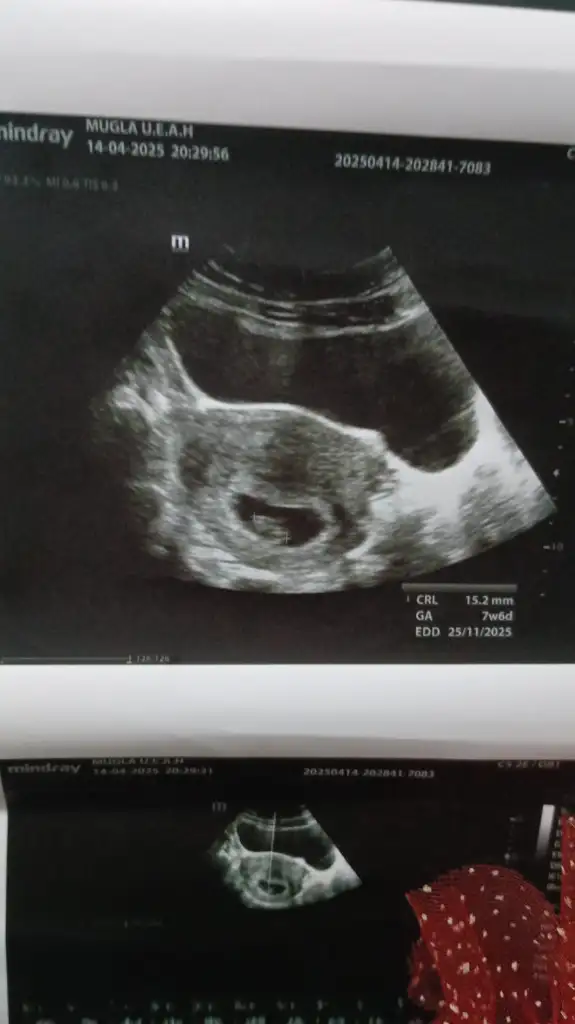

Çok geçmiş olsunMerhaba. Karından ultrasonla bakıldı. SAT’a göre 7+4’teyiz. Benim miniğime de bakar mısınız? Bir düşük tehdidi ile karşı karşıyaydık. 2 gün hastanede yatırdı beni yaramaz![]()